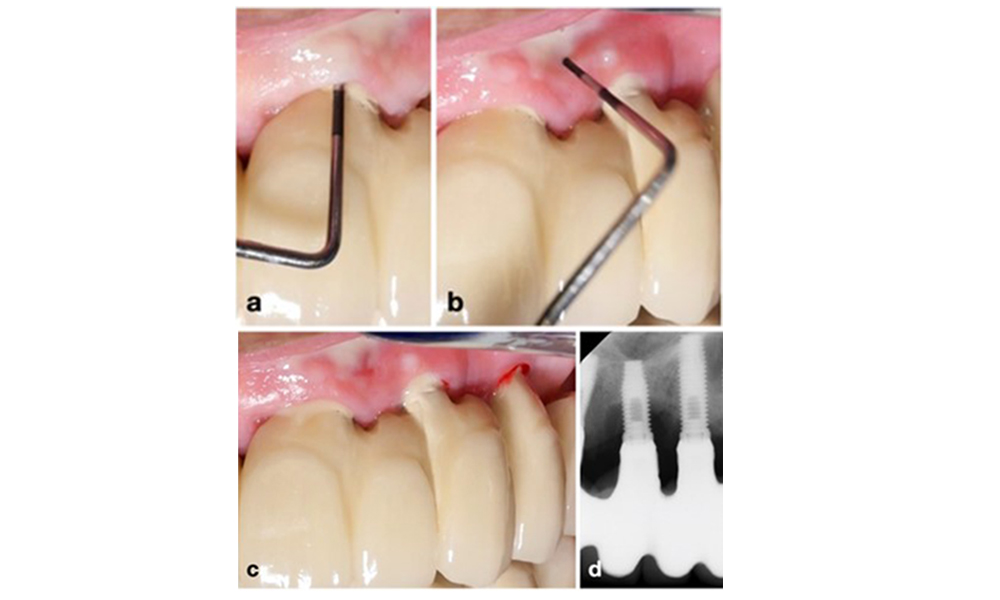

The prosthetic restoration should be removed during both non-surgical and surgical treatment to improve access to the implant surface. The choice of surgical intervention (e.g., resective, reconstructive, or combined) depends on several factors: (1) defect morphology (e.g., horizontal, dehiscence, intra-osseous, or combined) (figure 10), (2) implant surface (i.e., turned or modified/”rough”), and (3) presence or absence of sufficient keratinised and attached mucosa.

Defect morphology is one of the parameters defining the type of surgical intervention. While circumferential intrabony defects (a) can be treated well with a reconstructive approach, primarily horizontal bone defects (b) require a more resective approach.

Figure 10. Defect morphology is one of the parameters defining the type of surgical intervention. While circumferential intrabony defects (a) can be treated well with a reconstructive approach, primarily horizontal bone defects (b) require a more resective approach.